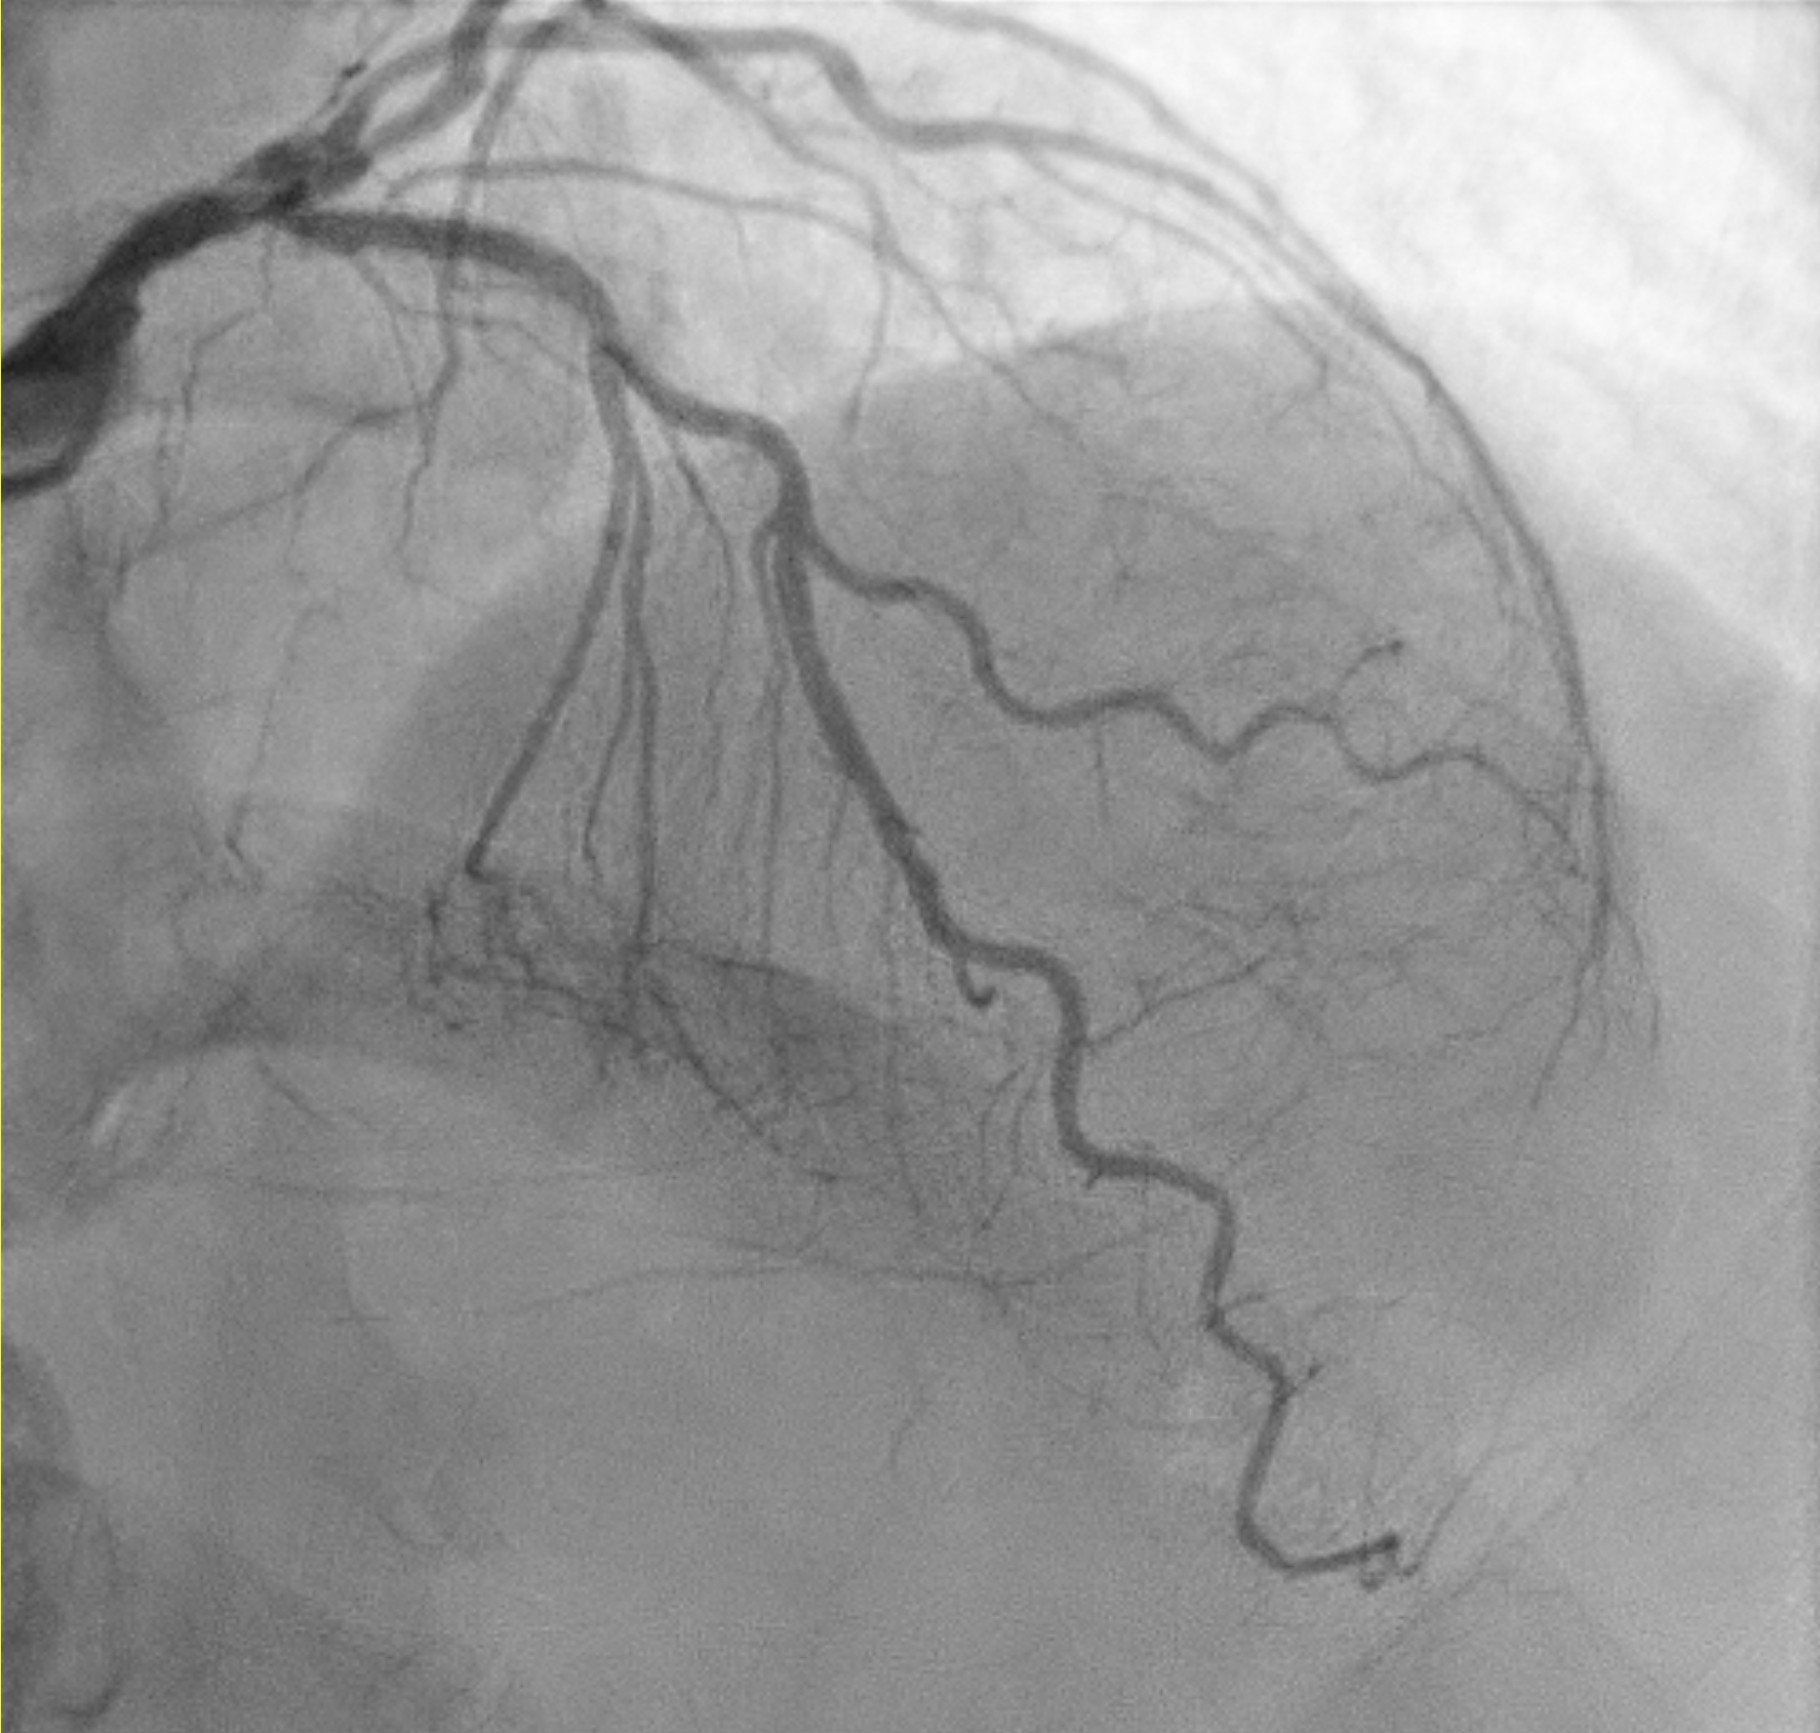

TRA diagnostic angiogram (pictures 1-3) showed mild distal LMS. Mild proximal-mid LAD stent <20% ISR and distal LAD 50% stenosis. Distal circumflex 50% stenosis. Proximal RCA 90% stenosis, distal 70% (segment 3) and then followed by total occlusion. Distal RCA received collaterals from LCA. Results discussed with patient who agreed for elective angioplasty to RCA.